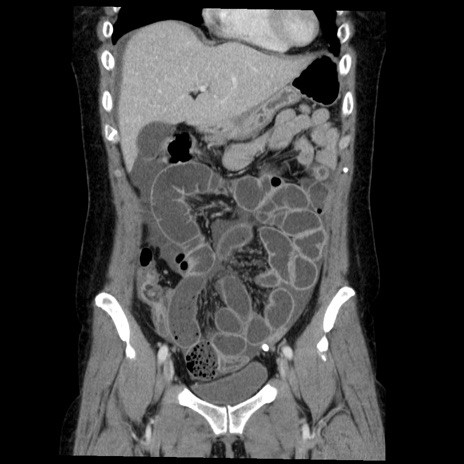

横断像

【症例】50歳代女性

【主訴】下腹部痛

【現病歴】本日朝より下痢2回あり。 昼食を食べた後、嘔吐3回、下腹部痛認め、症状軽快せず、当院救急搬送。

最終食事:本日昼(生ものなし)。 昨日の夜、刺身を食ぺたとのこと。周囲に同様の症状の者なし。普段、排便は毎日あるとのこと。

【既往歴】卵巣癌術後(8年前に当院で卵巣摘出)

【身体所見】 意識清明、腹部:平坦、腸蠕動音→、やや硬、下腹部自発痛・圧痛あり、反跳痛あり、筋性防御なし。

【データ】WBC 16000、CRP 0.01